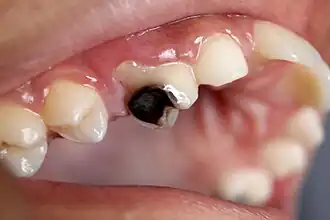

As the lesion continues to demineralize, it can turn brown but will eventually turn into a cavitation ("cavity"). A lesion that appears dark brown and shiny suggests dental caries were once present, but the demineralization process has stopped, leaving a stain. Active decay is lighter in color and appears dull.[14]

As the enamel and dentin are destroyed, the cavity becomes more noticeable. The affected areas of the tooth change color and become soft to the touch. Once the decay passes through the enamel, the dentinal tubules, which have passages to the nerve of the tooth, become exposed, resulting in pain that can be transient, temporarily worsening with exposure to heat, cold, or sweet foods and drinks.[15] A tooth weakened by extensive internal decay can sometimes suddenly fracture under normal chewing forces. When the decay has progressed enough to allow the bacteria to overwhelm the pulp tissue in the center of the tooth, a toothache can result, and the pain will become more constant. Death of the pulp tissue and infection are common consequences. The tooth will no longer be sensitive to hot or cold, but can be quite tender to pressure.

Dental caries can also cause bad breath and foul tastes.[16] In highly progressed cases, an infection can spread from the tooth to the surrounding soft tissues. Complications such as cavernous sinus thrombosis and Ludwig angina can be life-threatening.[17][18][19]